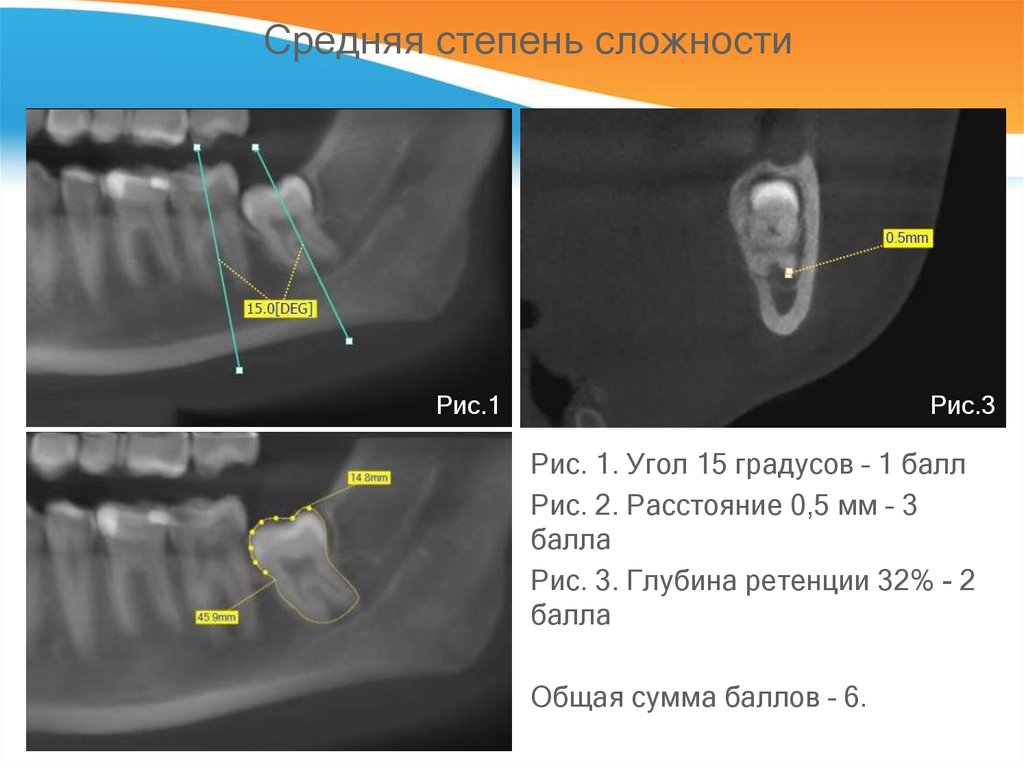

Ретенция код 119 фото